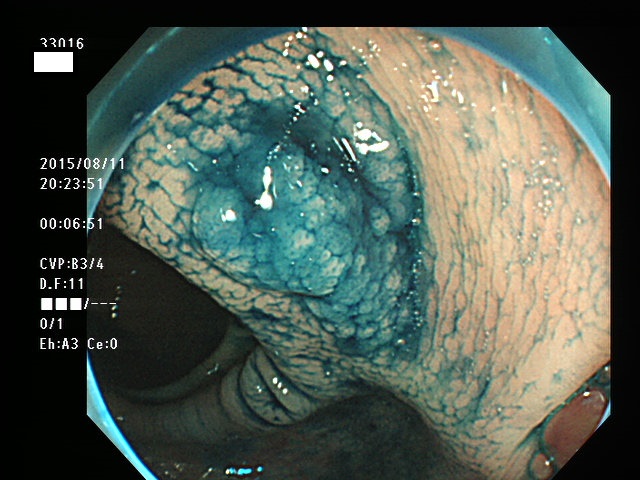

上記100名より抽出した平坦・陥凹型腺腫(=癌化の危険が高いが見落としやすい病変)の内視鏡写真

33003 33004 33005 33006 33007 33008 33009 33010 33011 33012 33013 33014 33015 13306 33018 33021 33024 33025 33026 33029 33030 33031 33032 33033 33036 33038 33039 33041 33042 33045 33046 33048 33051 33053 33054 33055 33057 33060 33063 33066 33068 33069 33071 33072 33074 33077 33078 33080 33086 33088 33089 33090 33091 33093 33095 33096 ・・・・・・の56名